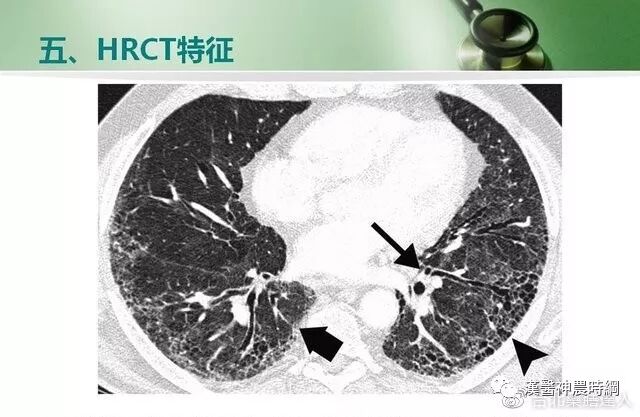

大多数间质性肺疾病都有共同的病理基础过程。初期损伤之后有肺泡炎,随着炎性-免疫反应的进展,肺纤维化泡壁、气道和血管最终都会发生不可逆的肺部瘢痕(纤维化)。炎症和异常修复导致肺间质细胞增殖,产生大量的胶原和细胞外基质。肺组织的正常结构为囊性空腔所替代,这些囊性空腔有增厚的纤维组织所包绕,此为晚期的“蜂窝肺”。肺间质纤维化和“蜂窝肺”的形成,导致肺泡气体-交换单元持久性的丧失。

肺纤维化发展过程中肺泡塌陷是失去上皮细胞的结果。暴露的基底膜可直接接触和形成纤维组织,大量肺泡塌陷即形成密集的瘢痕,形成蜂窝样改变。蜂窝样改变是瘢痕和结构重组的一种表现。肺脏损伤后,修复的结果是纤维化还是恢复正常解剖结构,取决于肺泡内渗出物及碎屑能否有效清除。

基于以上病理变化,临床上多表现为进行性呼吸困难或伴有刺激性干咳,胸部X线显示两中下肺野网状阴影,肺功能为限制性通气功能障碍。病情呈持续性进展,最终因呼吸衰竭而死亡。

早期虽有呼吸困难,但X线胸片可能基本正常;中后期出现两肺中下野弥散性网状或结节状阴影,偶见胸膜腔积液,增厚或钙化。肺组织纤维化的严重后果,导致正常肺组织结构改变,功能丧失。就是大量没有气体交换功能的纤维化组织代替肺泡,导致氧不能进入血液。患者呼吸不畅,缺氧、酸中毒、丧失劳动力、靠呼吸机生存,最后衰竭、死亡。